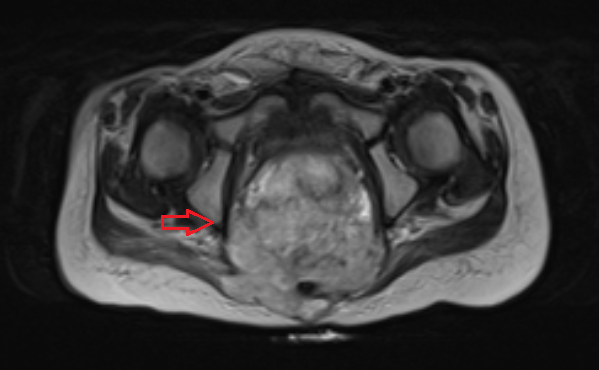

Яичники

Овариальные (расположенные в яичниках, яичниковые) опухоли наиболее часто проявляются болью в животе. При осмотре пальпируется опухоль в малом тазу, часто – в брюшной полости. Также за счет асцита (скопления в брюшной полости жидкости) увеличен живот. Нередко у девочек с таким диагнозом бывает лихорадка.

Самая часто диагностируемая герминогенная опухоль – это дисгерминома. Преимущественно ее обнаруживают во второй декаде жизни. У маленьких девочек встречается редко. Такое заболевания сравнительно быстро распространяется, поражая брюшину и второй яичник. Обычно новообразования односторонние, имеют большие размеры. В связи с этим частое явление – разрыв капсулы новообразования.

Risunok3b.pngРисунок 3. – тератома яичника а –УЗИ, б - МРТ.

Злокачественные тератомы обычно проявляются неспецифической клинической картиной, которая связана с наличием опухоли:

• увеличенный объем живота;

• боль;

• нарушение менструального цикла (наблюдается не всегда).